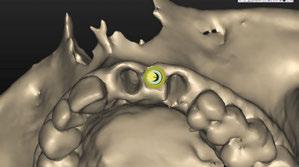

–Implante inmediato en incisivo lateral superior con técnica de «Socket Shield» y acceso vestibular para legrado de la lesión periapical, por el Dr. Ignacio Tormo Jiménez y cols. [106]

Planificación digital y cirugía guiada para dummies. Cómo confeccionar una guía quirúrgica de un modo predecible, por el Dr. Giuliano Fragola.